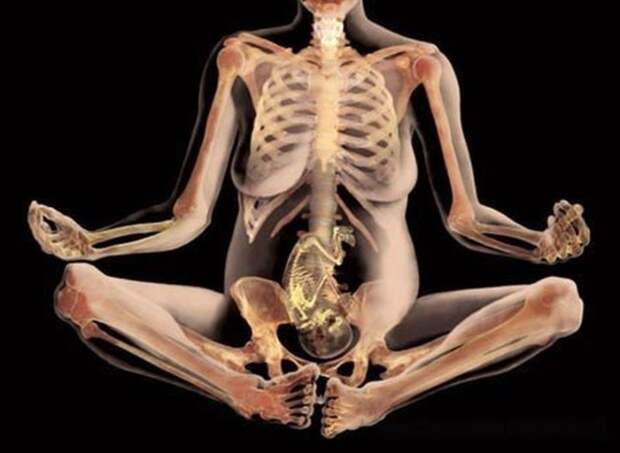

Таинство новой жизни